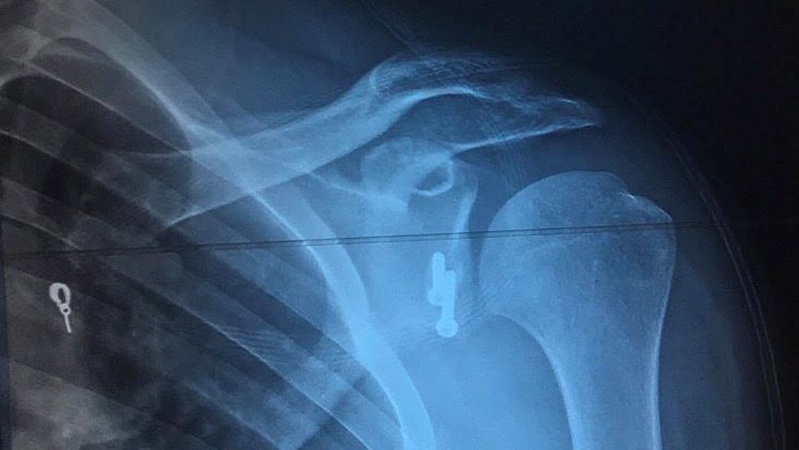

Хірурги Волинської обласної лікарні провели складну операцію військовому, в якого були численні вивихи плеча

«Хірургами відділення артроскопії та малоінвазивних отропедичних втручань Волинської обласної клінічної лікарні вперше проведена операція по стабілізації плечового суглоба з приводу звичного вивиху плеча (операція Латерже)», – йдеться у дописі.

Операцію провели військовому. Перший вивих він отримав під час бойових дій ще 10 місяців тому. Тоді його вправили товариші по службі самостійно й за медичною допомогою боєць не звертався. Орієнтовно через місяць стався повторний вивих плеча. Надалі вони повторювалися все частіше і частіше, навіть за найменших рухів. Коли чоловік вже не міг нормально рухати рукою, він звернувся за допомогою. Спершу військового направили у Дніпро, а тоді у Луцьк.

Хірурги Волинської обласної лікарні вирішили провести чоловіку операцію по стабілізації плечового суглоба за методом Латерже. Таке втручання має свої труднощі, оскільки є високий ризик пошкодити нервові та судинні структури кінцівки. Втім операція пройшла успішно, боєць уже може рухати рукою та проходить реабілітацію.